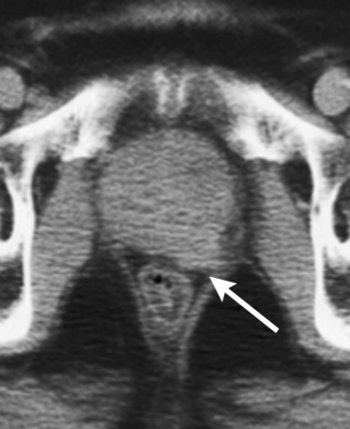

| Unenhanced CT scan in 78-year-old man with prostate cancer, Gleason score of 3 + 4 at biopsy, PSA level of 21 ng/mL, and palpable tumor shows enlarged prostate with evidence of gross tumor ECE (arrow) along left posterolateral margin of the gland. Figure 4. Hricak H, Choyke PL, Eberhardt SC, et al. "Imaging Prostate Cancer: A Multidisciplinary Perspective," Radiology 2007;243:28-53. |